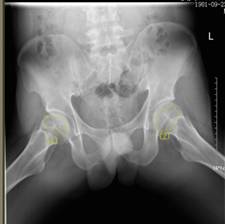

福音:微创治疗 增添保髋治疗新手段

据了解,PRP技术因其促进骨质再生及骨癒合的功能,同时因为血小板来源于自体,具有无免疫排斥、减少机体炎症和感染等优势,它常被应用于骨科特别是早期股骨头坏死及其他手术后加速癒合的治疗及运动损伤治疗上。该技术为微创手术,它的成功开展,增添了保髋治疗的手段,为患者带来了福音。